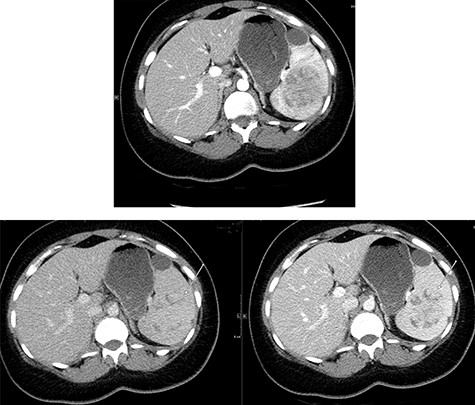

Abdominal ultrasonography showed a 5.0 × 5.0 cm well-defined, rounded, lobulated and hypoechoic vascular solid splenic lesion with no increased transmission or calcification. This lesion had vessels radiating from the center to the periphery (Fig. 1). Further evaluation with contrast-enhanced computed tomography (CT) of the abdomen showed a 6.0 × 5.6 × 4.4 cm solitary, rounded and lobulated non-calcified mass in the spleen, demonstrating heterogeneous, linear and nodular arterial enhancement with progressive filling in the portal venous and delayed phases (Fig. 2).

Top image shows abdominal CT scan arterial phase axial section with a hypodense, solitary, rounded and lobulated non-calcified mass lesion in spleen. Bottom right and left images show abdominal CT scan portovenous and delayed phase axial images showing a hypodense lesion and areas of filling (arrows in both images) which becomes mostly isodense to spleen; incidental finding of a splenic cyst.